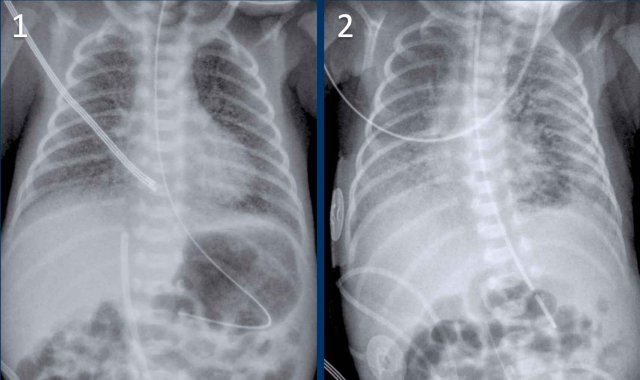

Premature of 25 weeks and 5 days, now 2 month old. Treatement for RDS

1. The first chest radiograph shows hyperinflation, and a markedly enlarged heart with increased vascular markings and interstitial markings.

NG tube and duodenal tube in situ.

2. After 5 days of treatment there is less hyperinflation and normalization of the heart size and vascular markings.

There still remain some interstitial markings, in keeping with BPD.